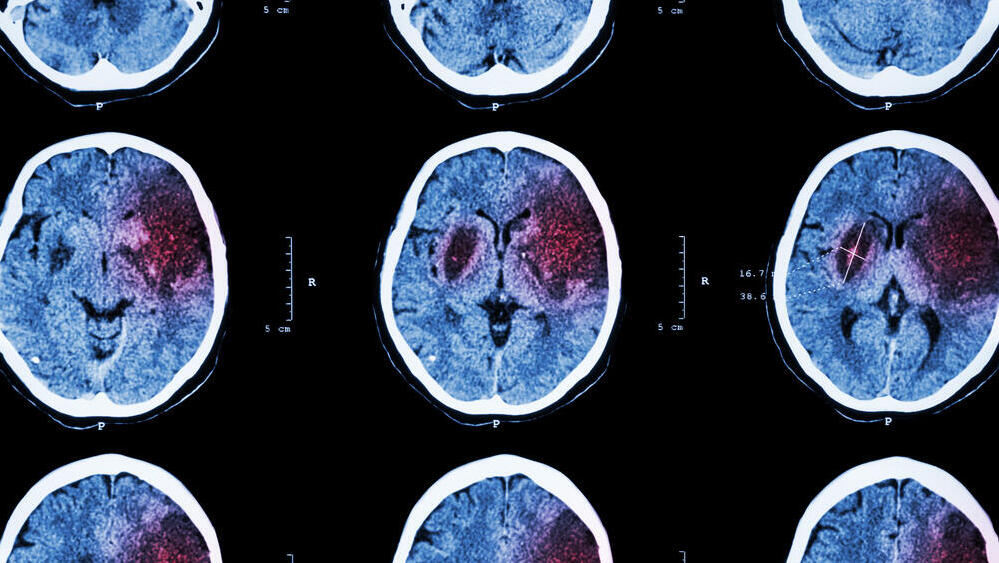

A. arrived at the medical center within an hour in a drowsy state, with mild left-side weakness that progressed to full paralysis. "After initial supportive care in the ER, imaging tests revealed signs of a dissection in a major artery on the brain's right side," Dr. Borodetsky explained.

"A dissection is the separation of the artery's layers, which can lead to blockage and stroke symptoms. While strokes in young patients are rare, one-quarter of such cases involve dissections."